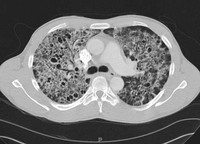

Computed tomography scan of the thorax showing bilateral pulmonary interstitial infiltrates and pneumatoceles (cysts), which are typical of Pneumocystis pneumonia (PCP)

From the collection of Matthew Gingo, UPMC